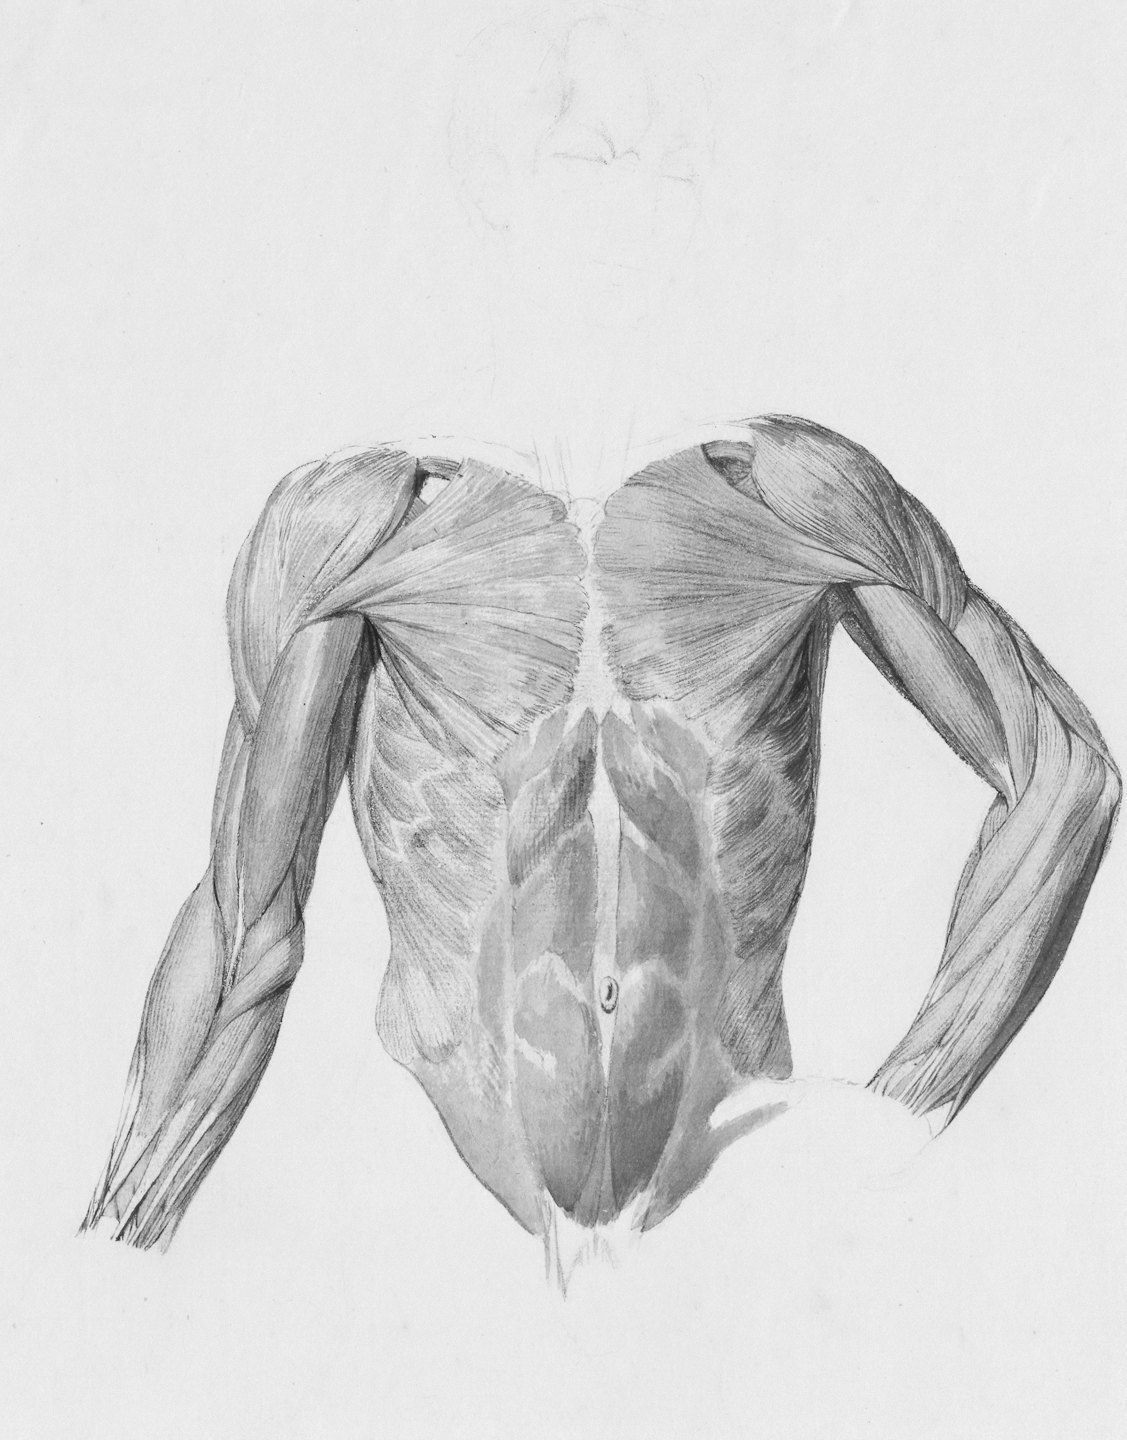

Aquí analizamos detalladamente la biomecánica de los brazos, mostrando cómo optimizar la hipertrofia de bíceps y tríceps con precisión científica.

Aplicamos cálculos de momentos de fuerza para maximizar el crecimiento muscular saludable.

Estudio detallado de la flexión y extensión del codo para mejorar la función muscular.

Esta sección presenta análisis técnicos y biomecánicos para optimizar el desarrollo de bíceps y tríceps.

Aquí encontrarás imágenes que ilustran la biomecánica y técnica para maximizar la hipertrofia muscular.